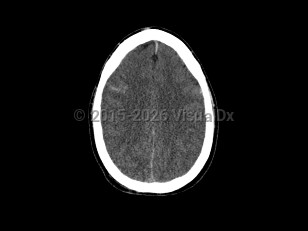

Vomiting, Headache, 50-59 year old Female

Subarachnoid hemorrhageSubarachnoid hemorrhage

Cerebral edemaCerebral edema

Hydrocephalus

Epidural intracranial hematomaEpidural intracranial hematoma

Subdural hematoma